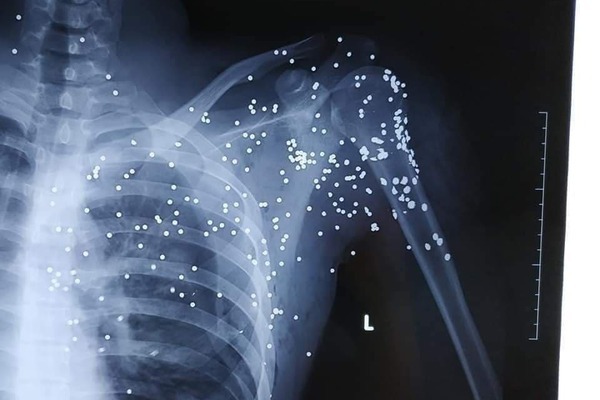

Nạn nhân bị trúng nhiều vết đạn và mất máu. Ảnh: Vietnamnet |

Kẻ lạ mặt này đi trên xe khách (chưa rõ biển số) có gắn logo của nhà xe Đ.T chạy tuyến Thái Bình - Hà Nội. Sau khi bắn anh H., đối tượng nhanh chóng rời đi. Anh H. ngã gục tại hiện trường và được mọi người đưa đến bệnh viện Đa khoa tỉnh Thái Bình cấp cứu, trong tình trạng đa chấn thương, mất nhiều máu. Kết quả chụp X.Quang cho thấy, anh H. bị đạn hoa cải găm chi chít tại vùng cổ, vai trái và phía trên ngực trái, mất nhiều máu.

Do vết đạn xuất hiện dày đặc nơi vùng phổi của nạn nhân, nên anh H. được chuyển lên bệnh viện Việt Đức (Hà Nội) để điều trị.

Kết quả chụp X.Quang ghi nhận đạn hoa cải trên cơ thể nạn nhân. Ảnh: Vietnamnet |